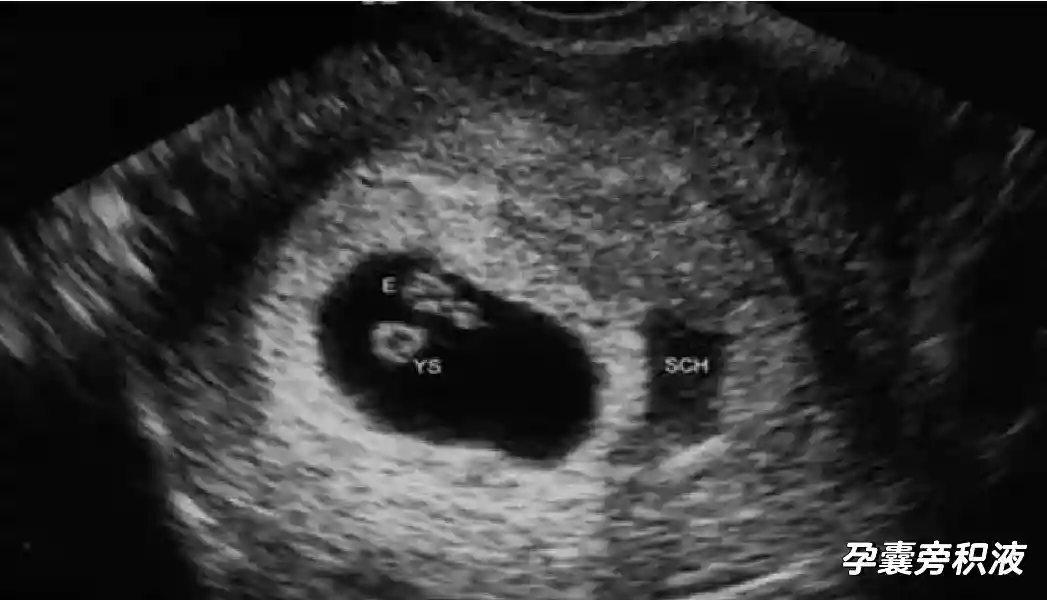

1??妊娠囊:早期妊娠囊:正常妊娠囊位于宮腔上段,表現(xiàn)為宮腔內(nèi)圓形或橢圓形的無(wú)回聲區(qū),周邊為完整的、厚度均勻的強(qiáng)回聲環(huán),強(qiáng)回聲環(huán)厚度≥2mm,強(qiáng)回聲是妊娠絨毛的回聲,隨著妊娠囊的增大,形成特征性的“雙環(huán)征” ,10周以后消失。正常的妊娠囊增長(zhǎng)速度是平均 1 mm /d。

2??卵黃囊:是妊娠囊內(nèi)第一個(gè)解剖結(jié)構(gòu),直徑<7mm。表現(xiàn)為小環(huán)狀,中央為無(wú)回聲,囊壁薄,內(nèi)透聲好。卵黃囊位于胚胎旁胚外體腔內(nèi)。卵黃囊通常在孕5-6周時(shí)出現(xiàn),5-10周穩(wěn)步增長(zhǎng),一般不超過(guò)7mm,至12周消失。妊娠囊的大小與卵黃囊之間有一定關(guān)系,妊娠囊平均直徑> 8 mm 時(shí),經(jīng)陰道超聲均應(yīng)顯示卵黃囊,妊娠囊平均直徑> 18 mm 時(shí),經(jīng)腹超聲均應(yīng)顯示卵黃囊。